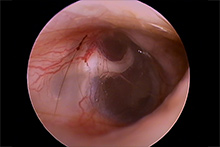

耳内視鏡(ビデオオトスコープ)で見た耳の状況

軽度~重度の症状の耳

犬の耳 2 猫の耳 1

猫の耳 1 猫の耳 2